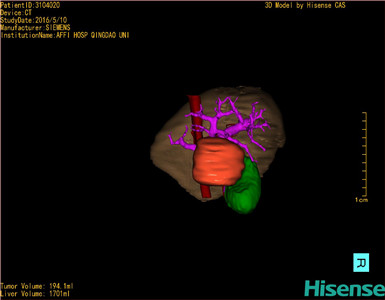

将0.625mm双源薄层CT资料的静脉期和动脉期Dicom格式文件导入海信CAS系统。

通过调节窗宽窗位调整CT序号,对肿瘤,肝实质,胆囊,下腔静脉,肿瘤,肝动脉、门静脉及肝静脉等进行三维重建;系统自动计算肿瘤体积和肝脏体积。

模拟手术操作,自动计算切除肿瘤体积。肝脏体积为1701ml,肿瘤体积为194.1ml,肿瘤体积为肝脏体积的11.4%,通过比对60-70岁正常肝脏体积为1262.7±284.31 ml,通过术前模拟手术,精准判断切除后剩余肝脏体积能耐受,避免肝衰竭发生。

术前手术方案的规划。

术前三维重建:

重建图片